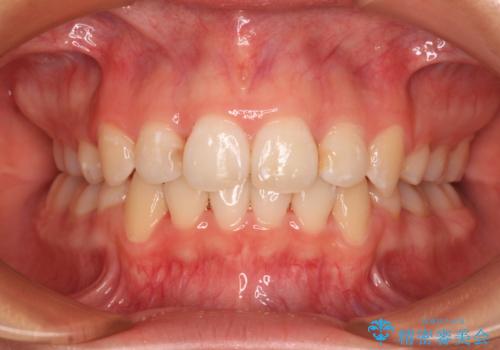

反対咬合とクロスバイトを改善して噛みやすい咬合に

- 前歯のデコボコとクロスバイトを気にして来院された患者様です。

骨格的に下顎が前方位の受け口傾向であり、それが原因でクロスバイトとなっていました。

受け口傾向の非抜歯矯正であったため、インビザラインによる矯正治療をお勧めしましたが、自己管理が面倒であるとのことで、ワイヤー装置にて行うこととしました。

なお、右奥の歯が180度回転した状態で萌出しており、こちらは改善困難なため、そのままの向きで配列することとしました。

右奥の歯が180度回転していることで、噛む度にワイヤーに無理な力がかかったようで、頻繁にワイヤーが切れてしまいました。また、下顎を後方に移動させるためのアンカースクリューも脱離することが多く、治療期間が長くなってしまいました。